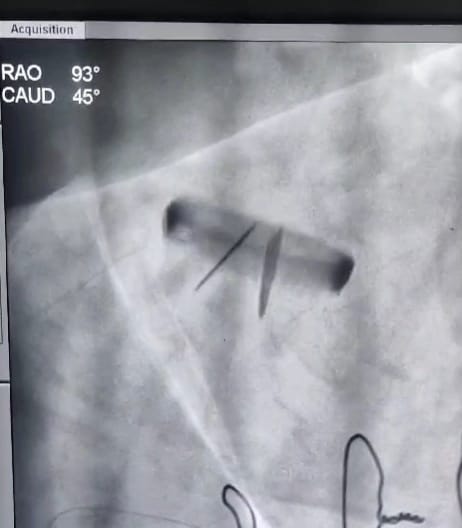

• Pacemaker implantation

• Implantable Cardioverter Defibrillator (ICD)

• Cardiac Resynchronization Therapy (CRT)